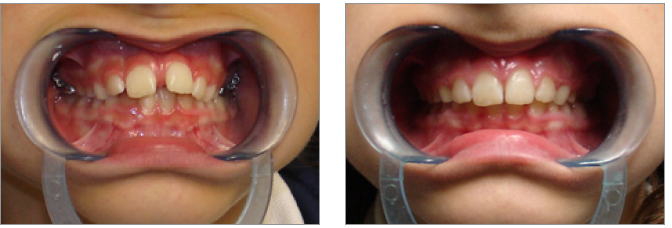

5) Le terapie ortodontiche eseguite in età precoce vanno sempre seguite fino a crescita scheletrica completa

6) Disallineamenti anteriori possono essere risolti con una terapia con mascherine per un maggior confort del paziente adulto

7) La terapia precoce deve eliminare elementi patogenetici di aggravamento come l’interposizione linguale

8) La precoce correzione del morso inverso elimina laterodeviazioni funzionali mandibolari